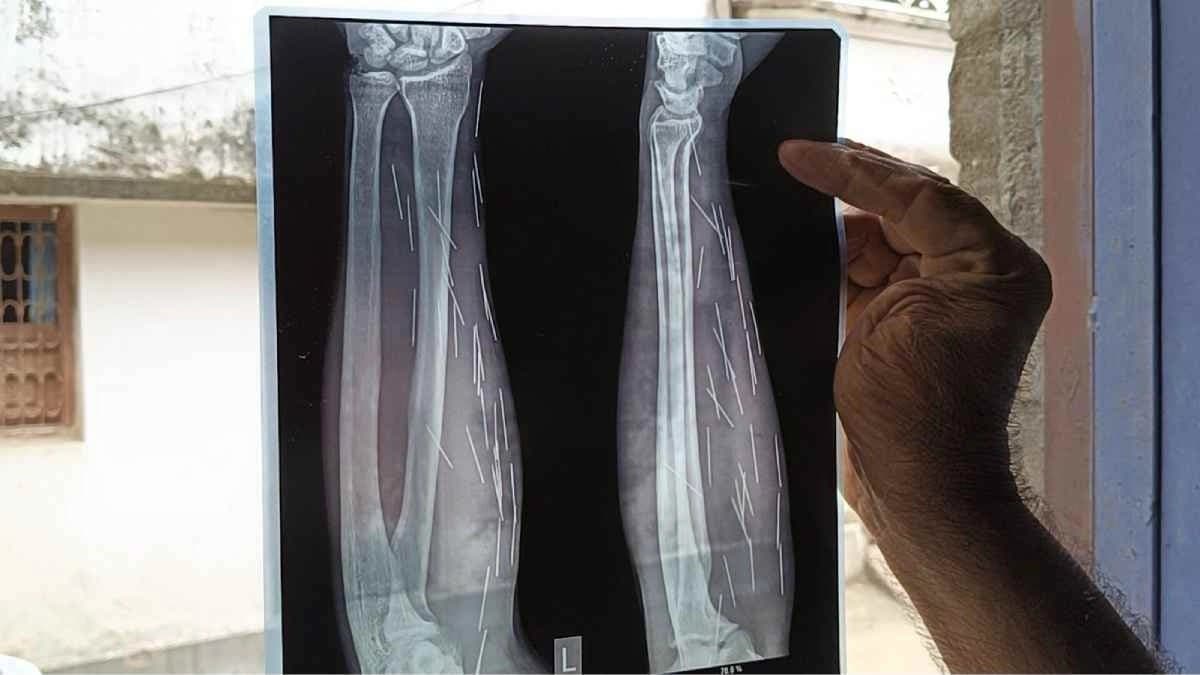

কালিয়াচকের বাধন এলাকায়। গত দেড় বছর ধরেই মূলত হায়দার আলির শরীরে এই সূচ-এর সমস্যা তৈরি হয়েছে। হায়দারের এক আত্মীয় মহম্মদ সাকির শেখ বলেন, 'গত দেড় বছর আগে হায়দার যখন শরীরের যন্ত্রণায় ছটফট করছিল তখন ওকে আমরা মালদা মেডিক্যাল কলেজে চিকিৎসার জন্য নিয়ে যাই। এক্সরের প্লেট চোখের সামনে তুলেই যেন সকলের চক্ষুচরক গাছ হয়ে যায়। হায়দারের হাতে, পেটে, পিঠে কিলবিল করছে সূচ। এই সূচগুলো কোথা থেকে এল তা আমরা কিছুই বুঝতে পারছি না।' গত দু'মাস আগে মুর্শিদাবাদের সামসেরগঞ্জের একটি নার্সিংহোমে অস্ত্রোপ্রচার করে হায়দারের শরীর থেকে দুই দফায় মোট প্রায় ৩০ টি সূচ বের করেছিলেন চিকিৎসকরা।

সেই সূচ বেশ বড় সাইজের। আবারও নাকি হায়দারের শরীরে অসংখ্য সুচ দেখা দিয়েছে বলে তাঁর দাবি। এদিকে হায়দারের শরীরের এই সূচ কাণ্ড নিয়ে রীতিমতো আতঙ্কিত পাড়া-প্রতিবেশীরা। স্থানীয় বাসিন্দা মহম্মদ আনারুল শেখ , যশোদা বর্মনদের বক্তব্য, এমন অসুখের কথা জীবনে কোনদিন শুনিনি। জীবন্ত মানুষের শরীরে অসংখ্য সূচ! এটা ভাবাই যায় না । এক্সরে করার পর হায়দারের দুই হাতে, পেটে অসংখ্য সূচ ধরা পড়েছে । এটা কী করে সম্ভব? এই ঘটনার পিছনে অবশ্যই কিছু অবৈজ্ঞানিক বিষয় জড়িয়ে রয়েছে বলে তাঁদের দাবি। যদিও এর পিছনে কালাজাদু বা অন্য কোনো কুসংস্কার জড়িত নেই বলে দাবি করেছেন পশ্চিমবঙ্গ বিজ্ঞান মঞ্চের জেলা সম্পাদক মনোরঞ্জন দাস।